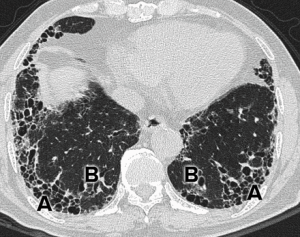

(2)CT對比解析度優於X線,套用高分辨CT(HRCT)可以進一步提高空間解析度,對於IPF的診斷,特別是早期肺泡炎與纖維化鑑別以及蜂窩肺的發現極有幫助。

(2)未行外科肺活檢的患者,胸部HRCT表現為肯定UIP型。